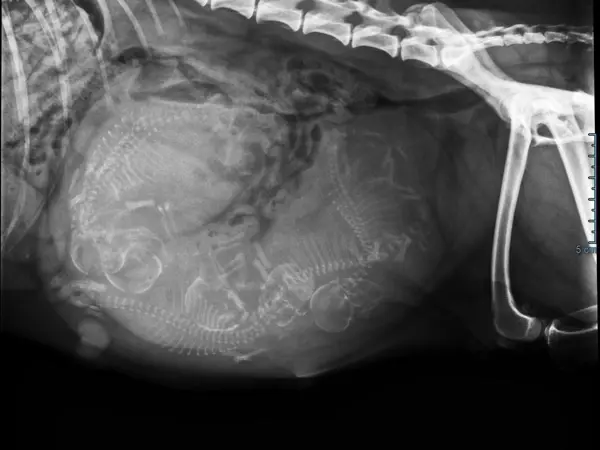

Dyreklinik - Ydelser

Vi tager os kærligt af dit kæledyr i vores moderne veludstyrede smådyrsklinik. Der er god tid til den enkelte patient, og der er fokus på tydelig kommunikation og trygge rammer for både ejer og patient.